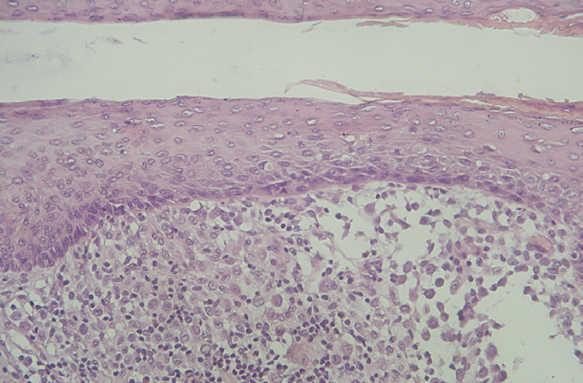

Las células de Langerhans son largas células ovoidales, de unos 12-15 mm de diámetro, de bordes mal definidos, con abundante citoplasma eosinófilo y un núcleo excéntrico en forma de «grano de café» (fig. 11). Como hemos adelantado, presentan marcadores inmunohistoquímicos característicos como S100, CD1a, CD45, HLA-DR, CD4, CD2 y T200 (fig. 12) 12. Comparten con el sistema monocito/macrofágico algunos antígenos comunes: CD1a, CD11 y CD45.

Fig. 11.--HCL cutánea, mostrando las células de Langerhans con su característico citoplasma eosinófilo y núcleo en forma de «grano de café». (Hematoxilina-eosina, x40.)

En la HCL el infiltrado se localiza normalmente en la dermis adventicial, y puede invadir la epidermis, produciendo clínicamente lesiones erosivas (figs. 13 y 14). En las formas nodulares puede invadir la hipodermis. En pacientes adultos se ha descrito la distribución del infiltrado alrededor de los anejos (figs. 15 y 16) 13. Aparecen otras células inflamatorias en número variable, sobre todo neutrófilos, eosinófilos, linfocitos y mastocitos y, en menor medida, células gigantes multinucleadas. De forma clásica se han descrito tres subtipos principales: proliferativo, granulomatoso y xantomatoso, que se intentan correlacionar con las diferentes formas clínicas. Histológicamente no existen diferencias entre la HCL y la reticulohistiocitosis congénita autoinvolutiva 7.

Fig. 14.--A mayor aumento, detalle del infiltrado en dermis reticular. (Hematoxilina-eosina, x20.)